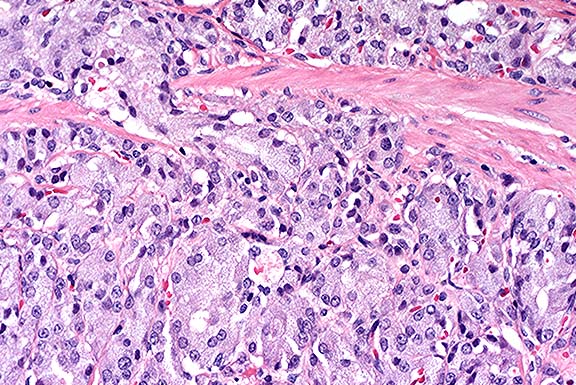

Case 5-4. Stomach. Demonstrates mucosal neuroendocrine carcinoma invading the submucosa. 20X

AFIP Diagnosis: Stomach: Neuroendocrine carcinoma, Sprague-Dawley rat, rodent.

Conference Note: Conference participants viewed a photograph provided by the contributor which demonstrated positive immunohistochemical staining for neuron-specific enolase in the neoplastic cells. In addition, by immuno-histochemistry performed at the AFIP, the neoplastic cells were positive for synaptophysin. The Churukian-Schenk method demonstrated numerous argyrophilic cytoplasmic granules.